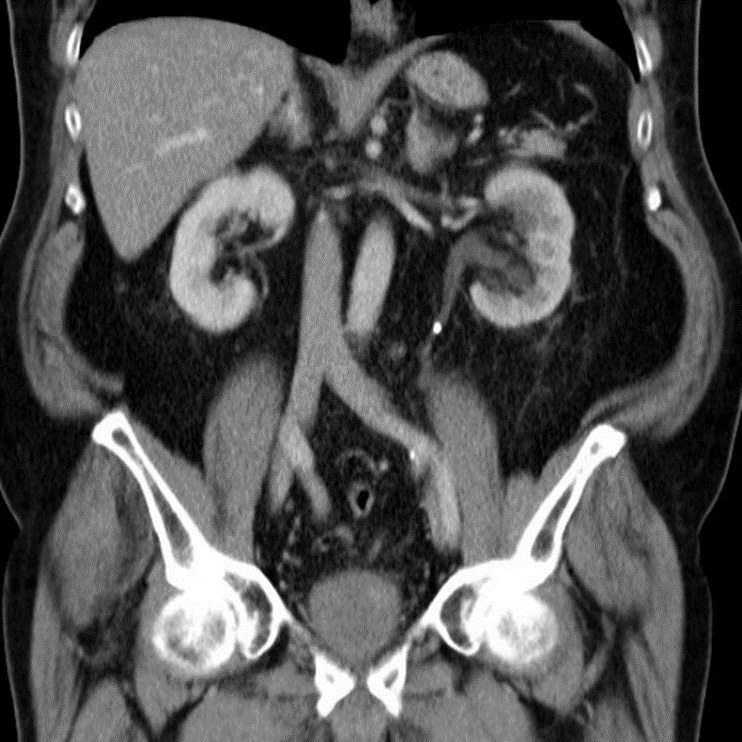

Abdominal CT with IV contrast (venous phase), coronal section

Hyperdense calculi located in the proximal third of the left ureter. As a result, the proximal ureter and the renal pelvis are dilated.